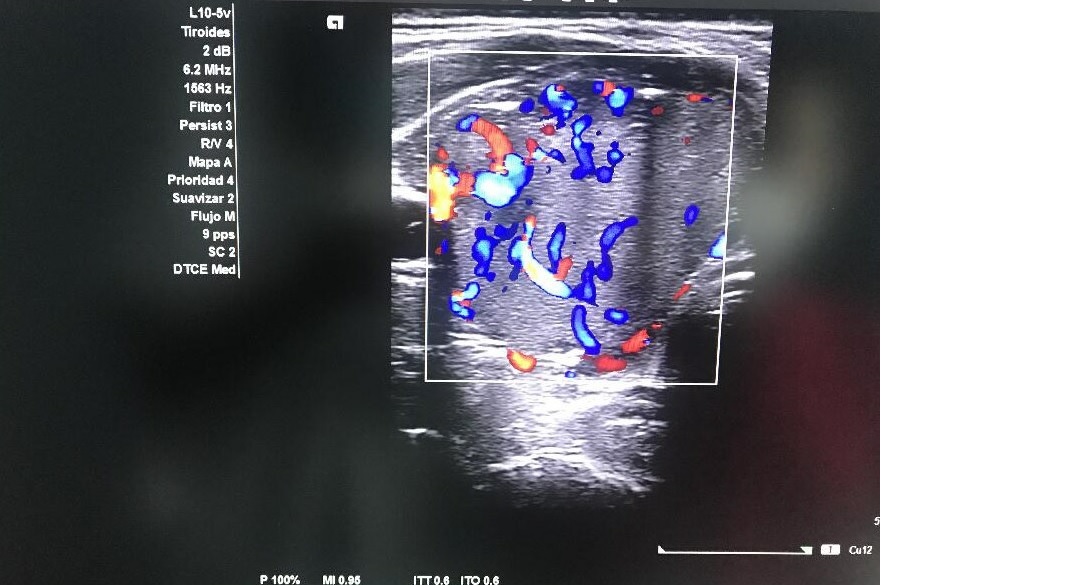

Ecografía tiroidea: Glándula tiroidea con ecoestructura homogénea en LTD con nódulo sólido en LTI con ocupación completa, hiperecogénico, bien delimitado con unas dimensiones de 3,5 x 3,5 x 4 con macrocalcificación en tercio superior con sombra acústica con vascularización de predominio periférico sin adenopatías cervicales.

Nodulo TIRADS 4 de 3,5 cm en LTI, sospecha de neoplasia folicular Bethesda IV.